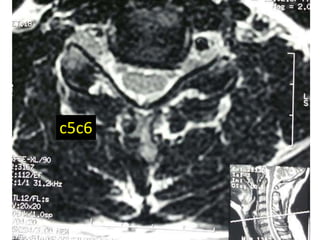

c5c6

48 year old man with right fifth finger pain and numbess

S/P C7T1

ACDF

persistent

symptoms of

ataxia, neck

pain, fine

motor hand

dysfunction